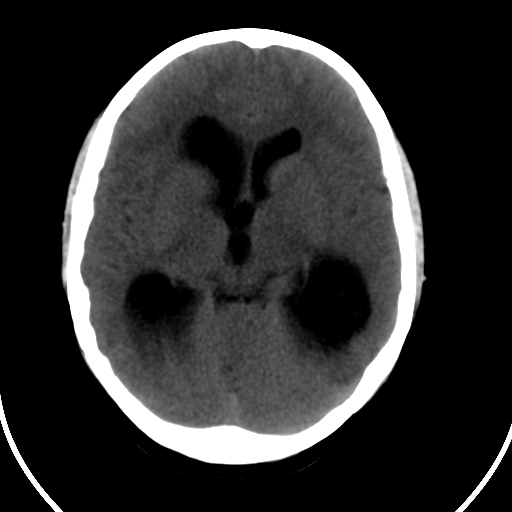

男,11岁

重度脑积水,但第四脑室扩大不明显,考虑导水管阻塞,建议mr。

右额叶单发近圆形低密度影,周边光滑,与侧脑室相通,考虑为孔洞脑并阻塞性脑积水。

右额叶内见一边界清楚,脑脊液密度的囊腔,无灰质内衬,并与脑室相通,四室以上脑室系统高度扩张。诊断:先天性脑穿通畸形伴梗阻性脑积水

需要与脑裂畸形鉴别:可见单侧或双侧衬有皮层的脑裂伸入额顶叶的白质内并与脑室相通